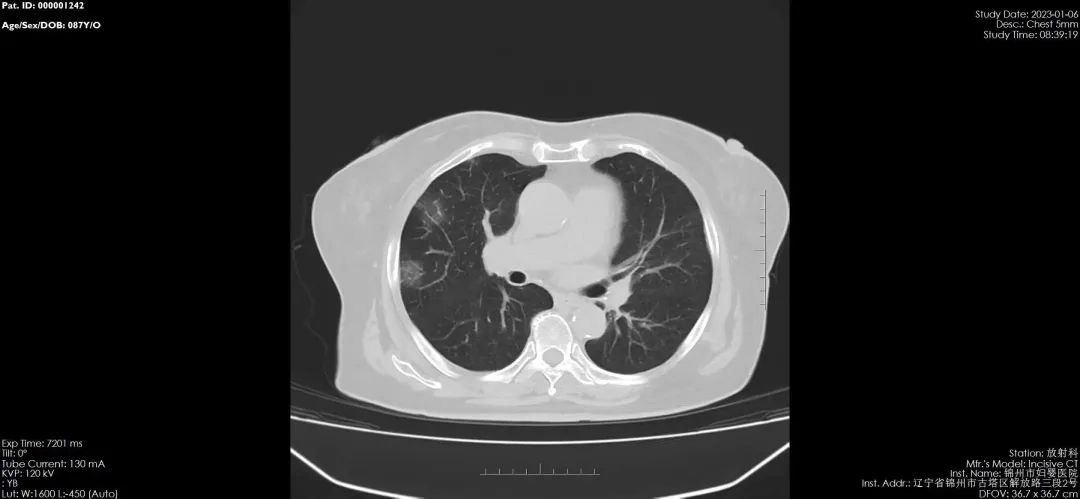

锦州市妇婴医院(妇幼保健院)放射线科,于2020年引进国内最新进口飞利浦64排128层螺旋CT,扫描速度快、分辨率高、层数更薄,对病毒性肺炎有着更高的检出率和准确率,可以更好的与其他肺炎进行区分,对早期肺炎治疗有着非常重要的临床意义。